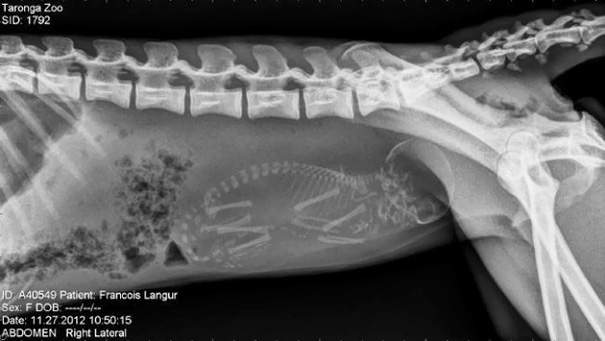

▼瀕臨絕種的黑葉猴

圖片來自:boredpanda